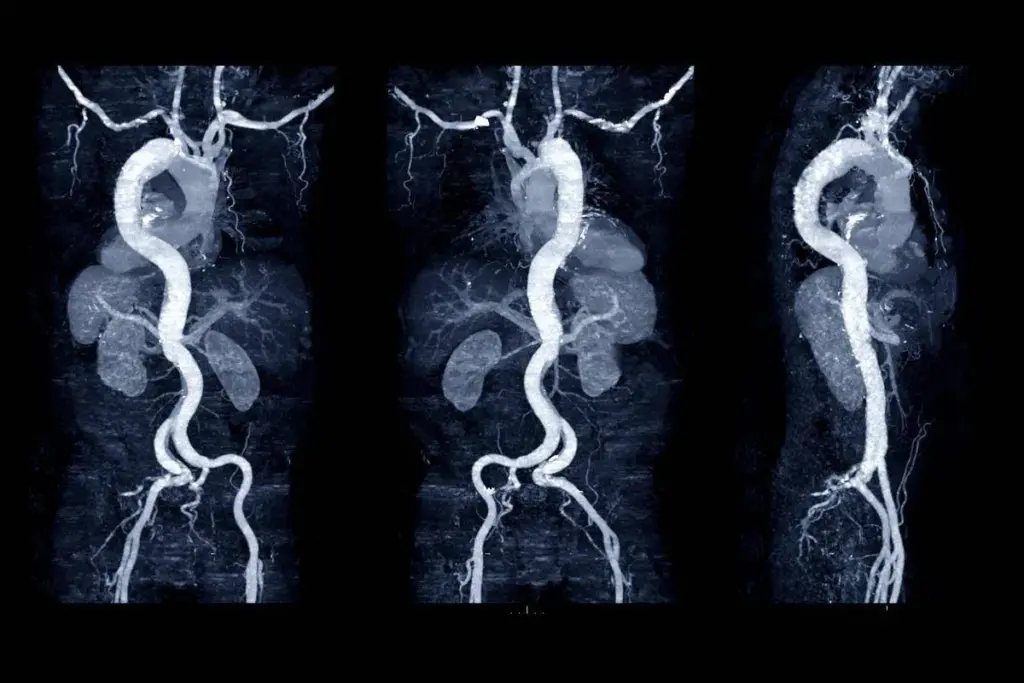

Aortic aneurysms are a serious condition where the aorta, the body’s largest artery, gets too big. This artery is key for blood flow to organs and tissues. An aneurysm happens when a part of the aorta weakens, causing it to bulge.

An aortic aneurysm is when the aorta gets bigger by at least 1.5 times its normal size. It can happen anywhere along the aorta, from the chest to the abdomen. Most of the time, aneurysms don’t show symptoms until they burst, making early detection very important.

The big worry with an aortic aneurysm is that it can burst, causing serious bleeding inside the body. The risk factors and how serious an aneurysm is can depend on where it is.

Abdominal Aortic Aneurysms (AAA)

AAAs happen in the part of the aorta in the belly. They are more common than thoracic aortic aneurysms and linked to smoking and hardening of the arteries. Like most aneurysms, AAAs usually don’t show symptoms until they burst, which is why screening is key for those at high risk.

TAAs happen in the chest part of the aorta. They are less common but can be more dangerous because they are close to the heart and can affect the aortic valve. TAAs are often linked to high blood pressure and certain genetic conditions.